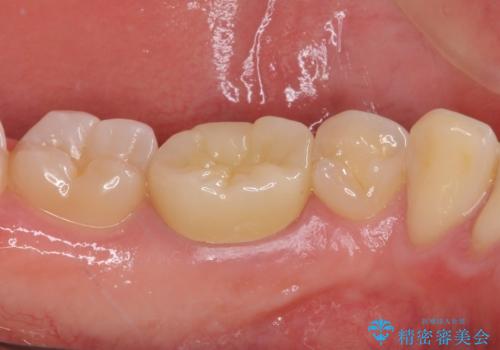

神経近くにまで及んだ大きなむし歯のセラミッククラウン

- 下顎左右奥歯に虫歯で痛みを感じるとのことで来院された患者様です。

むし歯が大きく、神経を取り除く可能性があることを理解いただいた上で虫歯を取り除き、その後はオールセラミッククラウンにて補綴することとしました。

虫歯除去後に痛みは収まり、神経も保存することができました。

変色していた歯もセラミッククラウンで自然な色合いとなり、患者様には大変満足していただきました。